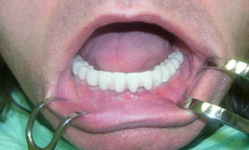

Pevné můstky – lepené nebo šroubované

Bezzubá čelist je hlavní indikací pro ošetření pomocí implantátů. Zejména celkové zubní náhrady v dolní čelisti mají velice nízkou stabilitu a držení díky velkému úbytku kosti.

S pomocí zubních implantátů můžeme díky různým kotevním systémům (třmeny, kulové hlavy, Locatory) zajistit stabilitu a držení protézy nebo při použití většího počtu implantátů zhotovit pevné náhrady – můstky nalepené nebo našroubované na pevno na implantáty.

S těmito typy náhrad můžeme dosáhnout perfektní funkci, výbornou estetiku, fonetiku a současně zajistit u pacienta možnost dobré hygienickou péče a čištění, která je pro životnost implantátů velice důležitá.